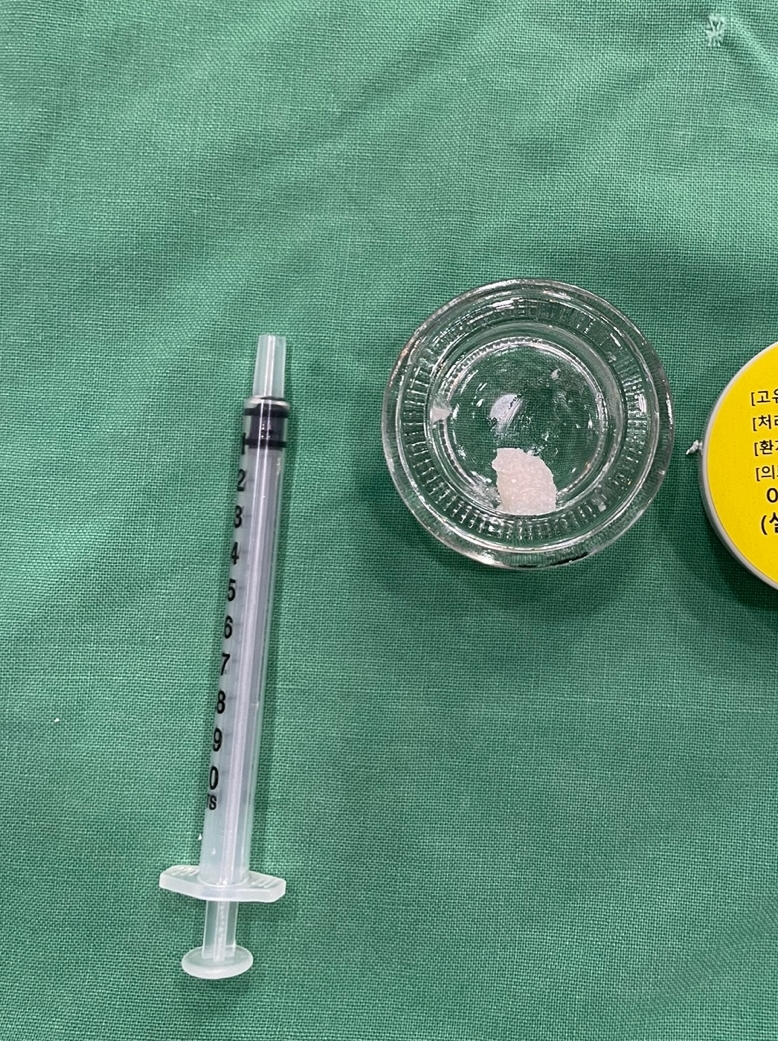

환자분과 보호자분께 상세히 설명드리고 자기치아뼈이식 상악동 거상술 그리고 수면마취로 진행해드렸습니다.

위의 사진을 본다면 구체적으로 어떤 방법으로 진행되는지 감을 잡을 수 있을 겁니다.